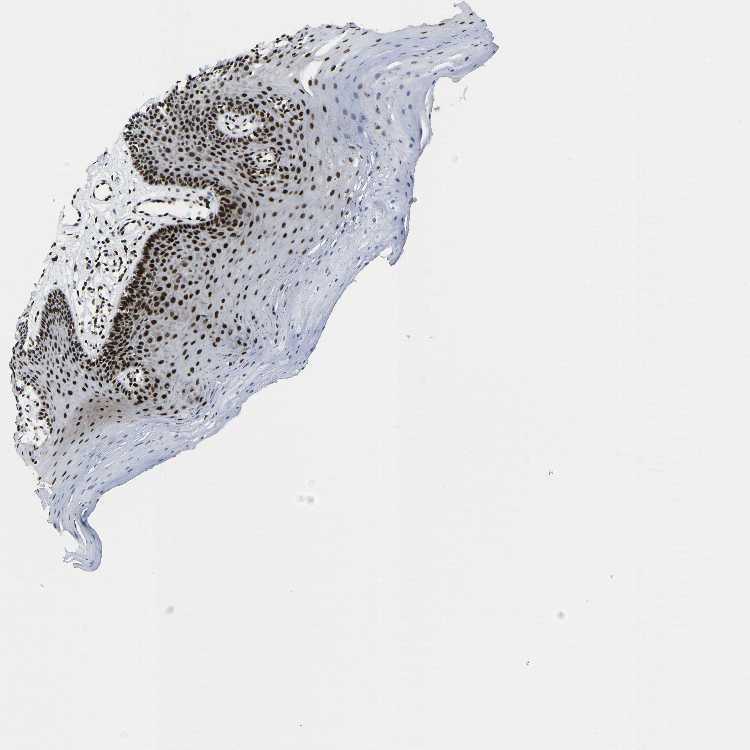

TISSUE PRIMARY DATA ORAL MUCOSA Show tissue menu

ORAL MUCOSA - Antibody stainingi

Antibody staining in the annotated cell types in the current human tissue is reported as not detected, low, medium, or high, based on conventional immunohistochemistry profiling in selected tissues. This score is based on the combination of the staining intensity and fraction of stained cells.

Each image is clickable and will lead to virtual microscopy that enables deeper exploration of all samples and also displays staining intensity scores, fraction scores and subcellular localization as well as patient and tissue information for each sample.

Antibody CAB013507

Squamous epithelial cells High